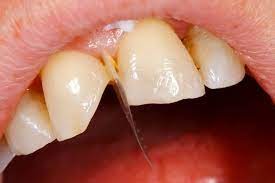

What Causes The Dark Line On My Gums?

You have seen smiles that you know have dental crowns in the front. You look at them and say to yourself that something is not natural. Many times, it is the dark rim of gum tissue that gives it away. The dark rim of gum tissue does not occur around natural teeth, only around teeth that have been covered with dental crowns.

The dark line is associated with an old porcelain dental crown. This style of dental crown is referred to as a porcelain fused-to-metal dental crown because it uses tooth-colored porcelain on the outside and it uses metal under the porcelain for strength. The dark line originates from the edge of the dental crowns where the porcelain and the metal meet at a knife-edge at the gum line. At the knife-edge, a very thin amount of the metal always shows. One of the illusionary techniques cosmetic dentists have used was to hide the thin dark line under the gum line. Over time, the gum tissue would recede and expose the dark line. In some patients the dark line would show through the gum and make it appear dark as well.